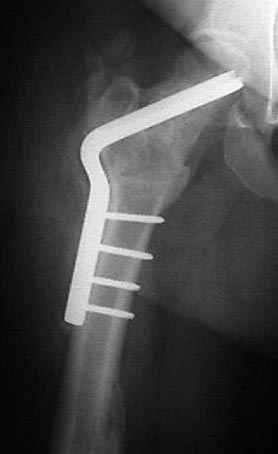

Если, например, доводится лечить больных с псевдартрозами шейки бедра, то надобность есть, и приходится. См. приложение.

На рисунке N1 предоперационный план лечения ложного сустава шейки бедра- линия ложного сустава, угол и направление введения импланта, клиновидная остеотомия в градусах и миллиметрах, второй снимок после коррекции, расчет, на сколько удлиняется конечность и размеры импланта;

N3 рисунок окончательный снимок, после операции моя рентгенограмма должен выглядеть примерно как эта картина. На N4 снимке клин перед удалением; N5 послеоперации 3 нед.; N6 окончательная рентгенограмма.

варус при проксимальном отделе 95 градусной пластиной.